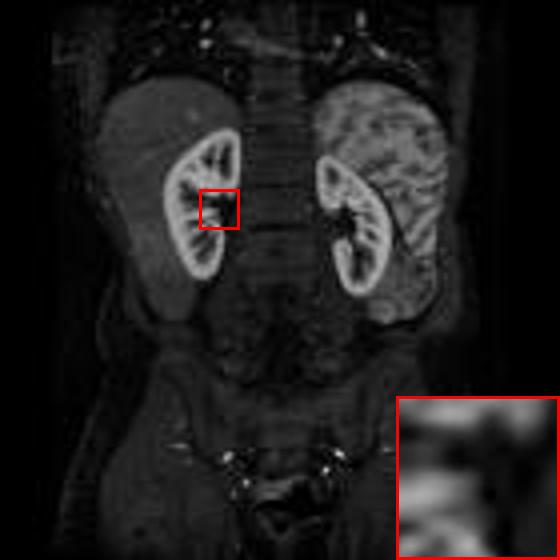

Figure 5: Reconstruction results of each algorithm for low-doze chest CT images.

III-D Super-resolution Reconstruction of Low-dose CT images

Medical pictures, such as computed tomography (CT) scans, are widely used in clinical applications such as noninvasive illness detection, anatomical imaging, and treatment planning, all of which need judgment while doing CT scans. These imaging approaches, however, have some drawbacks. During CT scans, for example, radiation damage is unavoidable. Low-dose CT (LDCT) is currently the clinically recommended strategy for preventing irreversible radiation harm to the body, however it comes at the cost of getting CT pictures with low resolution or noise contamination. The spatial resolution is generally coarser than that of CT imaging in order to get images with a high signal-to-noise ratio. As a result, obtaining high-resolution scanned images with a low-dose CT scanner is now a challenge.

In this section, we selected chest CT images of COVID-19 patients in an actual hospital [26] for our experiments. The visualization results of the experiments are shown in Figure 5 and Figure 6. The experimental results show that our proposed T-GAN is also applicable to the super-resolution reconstruction of low-dose CT images, and the high-resolution images obtained by our model have more detailed information compared with the baseline algorithm.